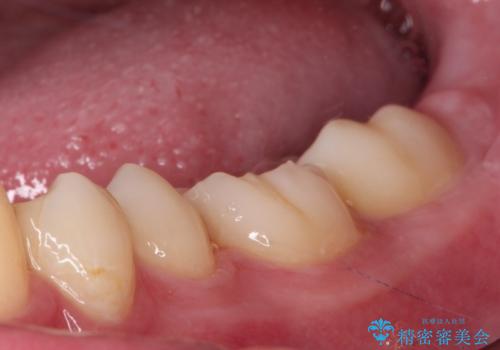

食べ物がはさまりにくくなり、冷たいものがしみる症状もなくなり、大変満足していただきました。

放置しても良いことはないため、もし詰め物がかけてしまったのに気が付いたら早めに歯科医院を受診されるのをお勧めいたします。